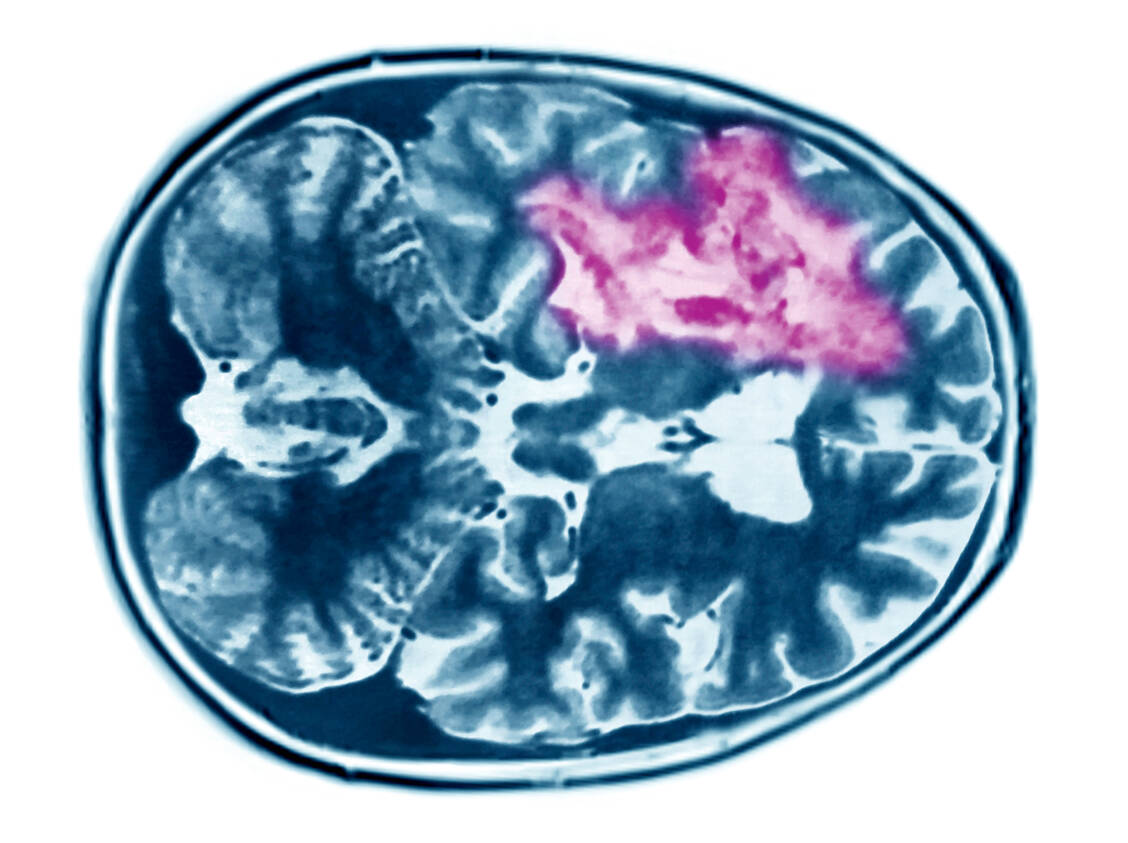

Glioblastome gehören zu den häufigsten und bösartigsten Hirntumoren bei Erwachsenen, auch wenn diese Tumorart insgesamt als selten gilt. Die Inzidenz liegt in Europa und den USA bei 2,9 bis 3,5 Neuerkrankungen pro Jahr pro 100.000 Einwohner. Das entspricht bis zu 2900 Neuerkrankungen pro Jahr in Deutschland.

Der Tumor kann in der Regel nie komplett chirurgisch entfernt werden, da meist bereits einzelne Tumorzellen gesundes Gehirngewebe infiltriert haben. Praktisch immer sind eine Bestrahlung und eine Chemotherapie nötig. Zur Erstlinientherapie zählt dabei das Prodrug Temozolomid. Das Gesamtüberleben liegt jedoch trotz dieser Behandlung in den meisten Fällen bei weniger als zwei Jahren, auch weil Glioblastome meist Resistenzen gegen das Alkylans entwickeln. Es wird vermutet, dass dies an Krebsstammzellen liegt, die als potenzielles Target für eine kurative Therapie gelten.